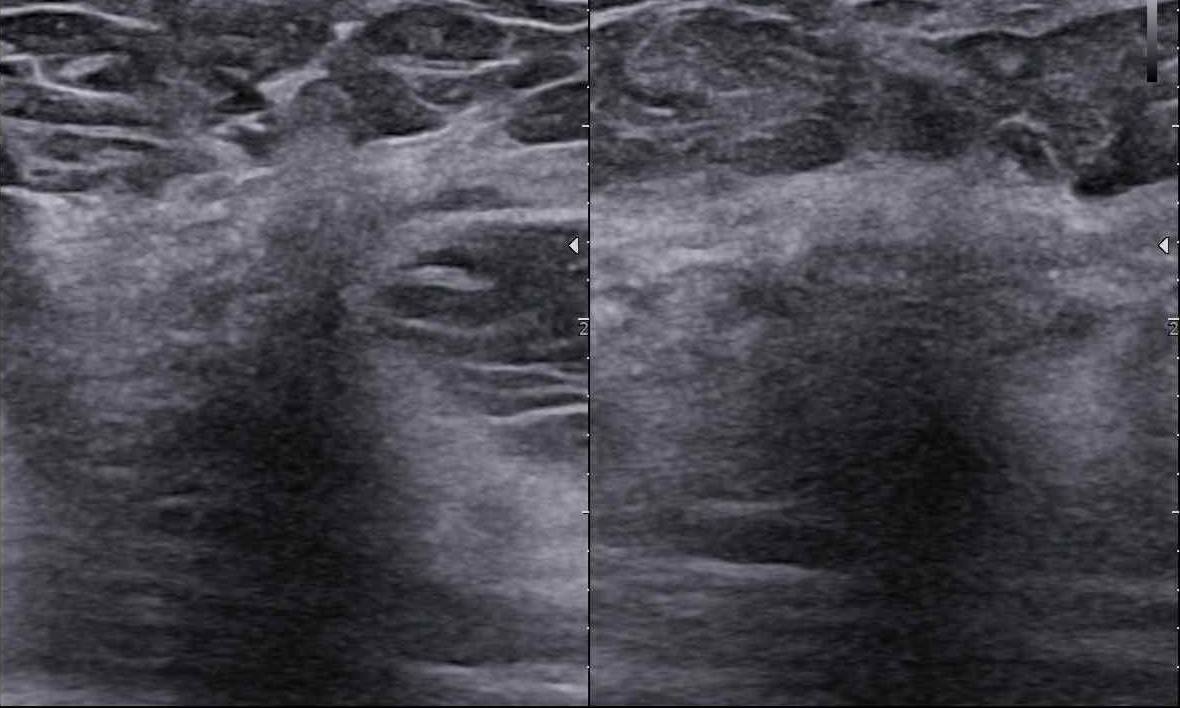

Czy podział BIRADS 4 ma sens? Jak radzić sobie z BIRADS 4a, b, c?

Czy my rzeczywiście potrafimy czytać tę skalę? Dlaczego tyle jest rozbieżności?